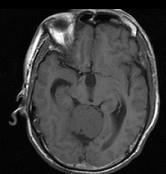

问题 男,61岁,头晕头痛伴行走不稳1月余,请根据所提供图像,选择最可能的诊断()

选项 A.胶质瘤 B.髓母细胞瘤 C.(天幕切迹缘)脑膜瘤 D.转移瘤 E.淋巴瘤

答案 C